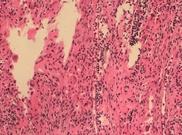

小兒海藍組織細胞增生癥

• 小兒海藍組織細胞增生癥